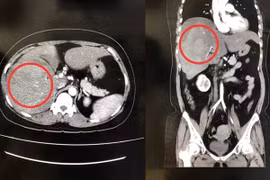

Bệnh nhân bị tai nạn giao thông ngã xe xuống cống chấn thương vỡ gan độ IV, sốc mất máu, huyết áp tụt 80/40mmHg. Vỡ gan nếu không phát hiện kịp thời dẫn đến chảy máu ổ bụng, sốc do mất máu và dễ tử vong nên cần nhận biết sớm.